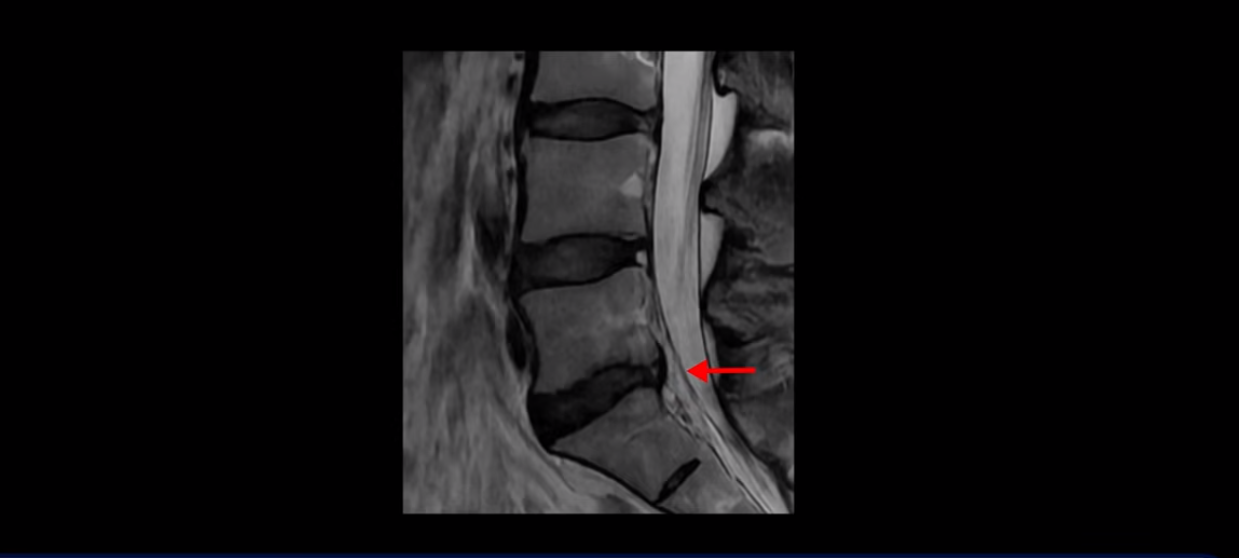

우선 이분 허리 MRI를 보면 5번 1번에 퇴행성 디스크가 있지만 방사통을 일으킬 만큼 신경을 누르고 있어 보이지 않습니다.

오른쪽으로 디스크가 약간 찢어져 보이는데, 작년에 찍은 MRI에서도 보이는 것이라 오래 전에 찢어진 후 아문 흔적으로 보입니다.

중요한 것은 오른쪽 다리에 심한 방사통이 있다든가 재채기를 못 한다거나 허리를 구부리거나 몸을 살짝 비틀 때 날카로운 통증이 없습니다. 즉, 섬유륜이 최근에 찢어진 게 아닌 겁니다.

4번 5번과 3번 4번 마디도 디스크가 중앙으로 살짝 밀려나와있지만 최근에 섬유륜이 찢어진 것도 아니고, 신경 다발을 누를 정도로 심하게 밀려나와 있는 것도 전혀 아닙니다.

양쪽 신경 가지가 빠져나가는 추간공도 충분히 넓어서 신경학적 방사통을 일으킬 여지가 없습니다.

그럼 이 환자분의 양쪽 다리 저림과 발 저림 그리고 앉기만 하면 5분 내로 심한 허리 통증, 엉덩이 통증이 발생하는 원인은 뭘까요? 저희가 이런 디스크 내장증 얘기를 들으신 환자분들 치료 후기에서 수없이 설명하지만, 이런 증상이 디스크가 원인이 아닙니다. 이분도 여러 병원에서 증상과 MRI가 일치하지 않는다고 들으셨는데요.